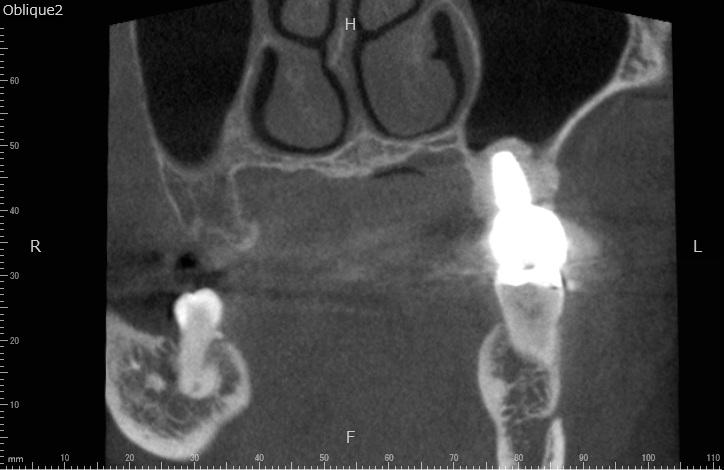

歯科用CTによる精密な検査

当院では必ず精密検査として、歯科用CTによる撮影を行います。顎の骨の状態、血管・神経の位置を正確に把握することで、手術の安全性が高まります。

CT画像は、インプラントの埋入のシミュレーションにも使用します。

2検査・診断

虫歯や歯周病の検査、レントゲン検査、CT検査などを行います。CT検査は、顎の骨の状態、血管・神経の位置を正確に把握し、シミュレーションをするために不可欠な検査となります。